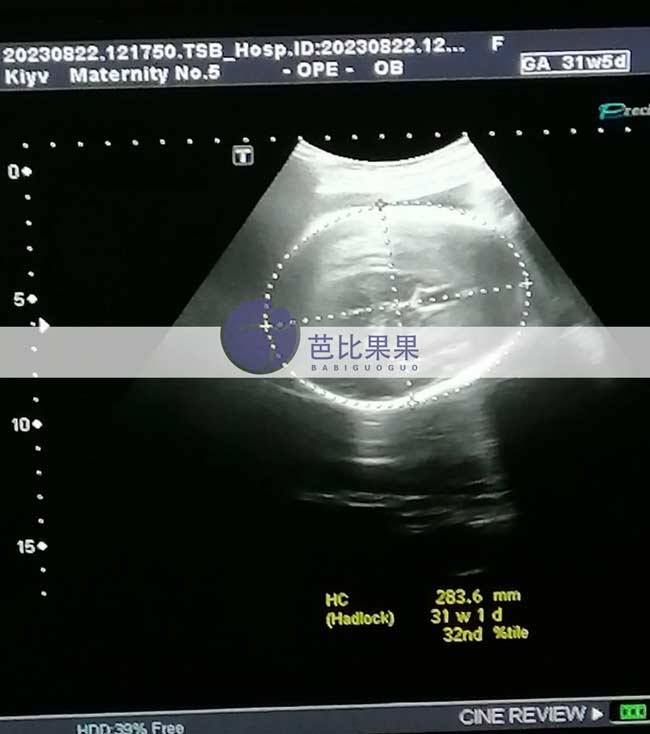

Z先生的乌克兰试管妈妈按时来做孕31周+的B超

Z先生家的乌克兰试管妈妈按时来做了孕31周+的B超,胎儿已经越来越大了,期待TA的到来